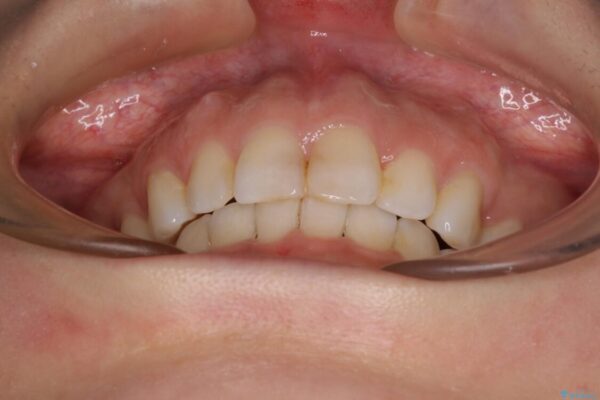

口元の閉じにくさと、奥歯の咬み合わせを気にして来院された患者様です。

左下の大臼歯2本が顕著に舌側に傾斜しているため、まずは奥歯の咬み合わせを改善をし、その後上下左右の第1小臼歯4本を抜歯することで口元を引っ込めながら整えることとしました。

治療後について

奥歯の咬み合わせ改善には1年ほどの期間と処置中の噛みにくさを強いることとなりましたが、抜歯後はスムーズに治療を完了させることができました。

歯ぎしりの際に奥歯が干渉していた咬み合わせも理想的な状態に改善できました。

治療前

• 【モニター】出っ歯と咬み合わせを改善 ワイヤー装置の抜歯矯正 治療前画像